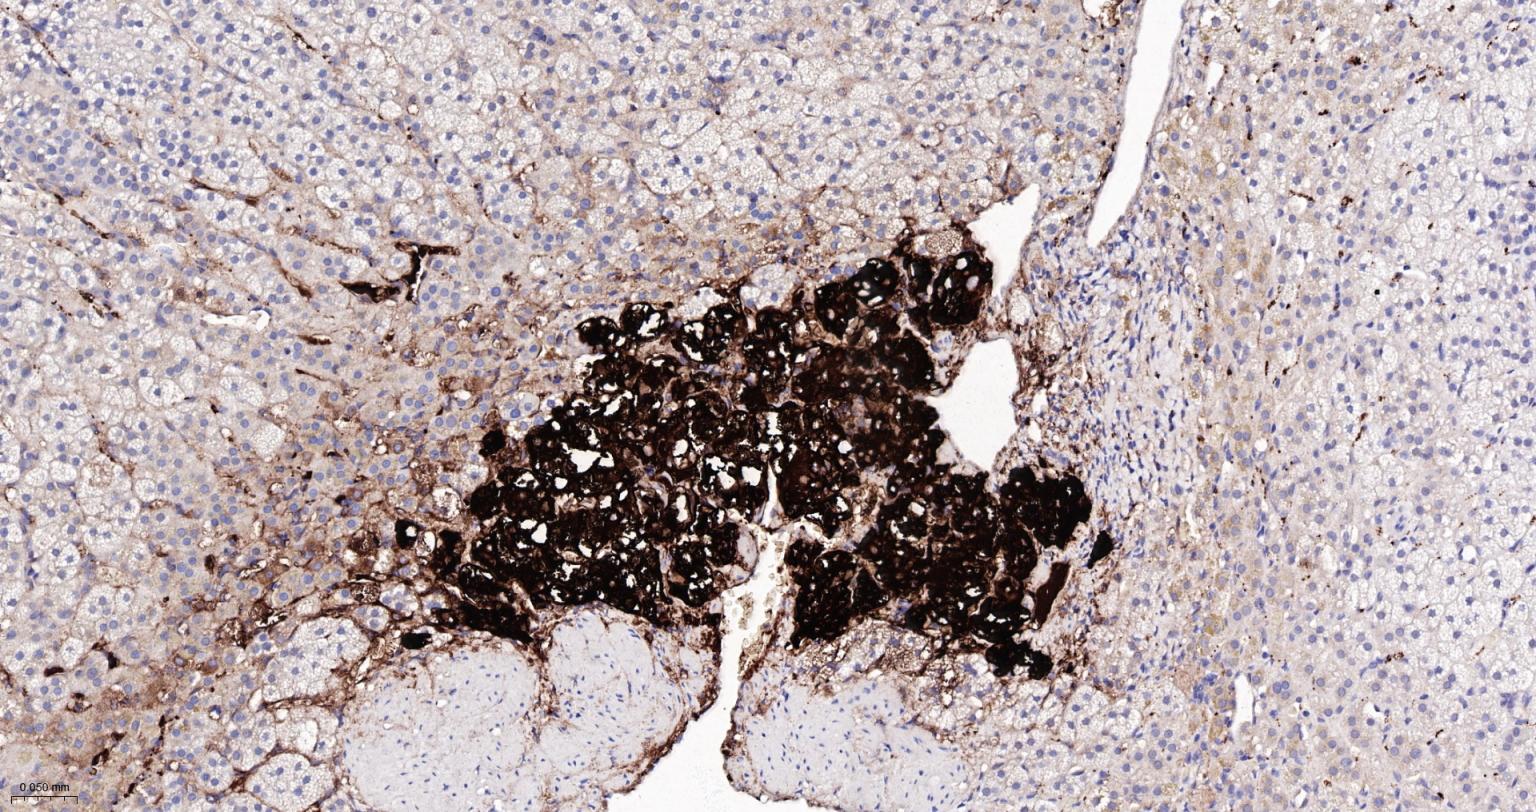

Paraformaldehyde-fixed, paraffin embedded Rat Adrenal Gland; Antigen retrieval by boiling in sodium citrate buffer (pH6.0) for 15 min; The section was incubated with Tyrosine Hydroxylase Monoclonal Antibody, Unconjugated (bsm-52574R) at 1:200 overnight at 4°C, followed by conjugation to the bs-0295G-HRP and DAB (C-0010) staining.

Paraformaldehyde-fixed, paraffin embedded Mouse Adrenal Gland; Antigen retrieval by boiling in sodium citrate buffer (pH6.0) for 15 min; Antibody incubation with Tyrosine Hydroxylase Monoclonal Antibody, Unconjugated(bsm-52574R) at 1:200 overnight at 4°C, followed by conjugation to the bs-0295G-HRP and DAB (C-0010) staining.